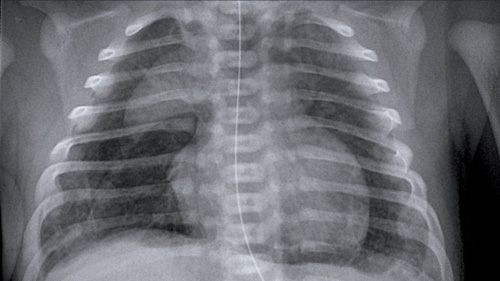

Neonatal Chest X-Ray